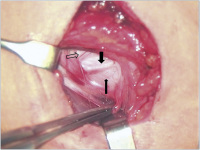

Elektrodenrevision

Abbildung 3: Intraoperativer Situs bei Elektrodenrevision. Das Kabel ist angeschlungen, die A. carotis freipräpariert (umrandeter Pfeil). Der N. vagus ist mit Narbenpaket andeutungsweise in leicht bogenförmigem Verlauf zu erkennen (schmaler Pfeil), an dem die Anode aufliegt (dicker Pfeil).